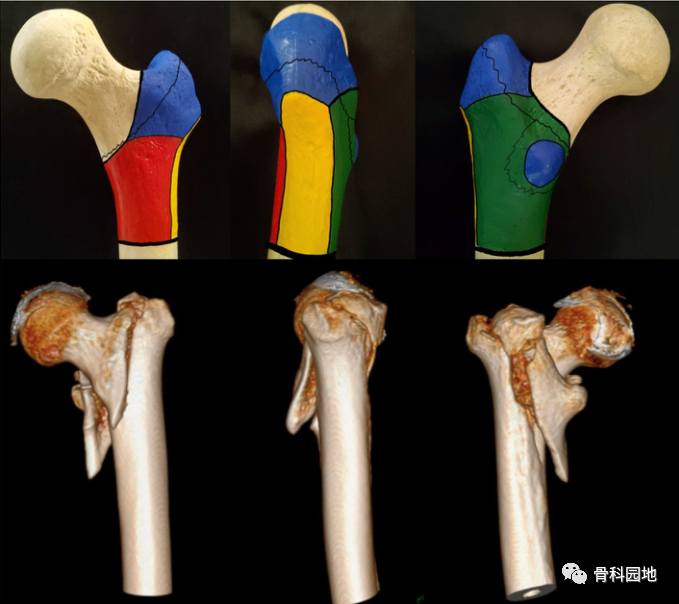

大腿骨近位部骨折:大腿骨頚部・転子部・転子下骨折の手術手技。股骨粗隆间骨折基于CT三柱理论分型方法- 好医术文章- 好医术-赋。Hip Arthroscopic OAT (Mosaic plasty) 股関節鏡視下骨軟骨移植。大腿骨近位部骨折の手術手技に関する専門書。裁断済みスキャン済みのためヨレや小傷はあります業者に裁断してもらいました書き込みはありません価格交渉やまとめ買いはご相談ください。Hip Arthroscopic OAT (Mosaic plasty) 股関節鏡視下骨軟骨移植。- タイトル: 大腿骨近位部骨折 Osteosynthesis & Arthroplasty- 著者: 高平尚伸, 鈴木恵美, 神田善男, 北田貴司- 内容: 大腿骨頚部・転子部・転子下骨折の手術手技に関する専門書- 出版社: メディカ出版- ISBN: 9784840451003ご覧いただきありがとうございます。